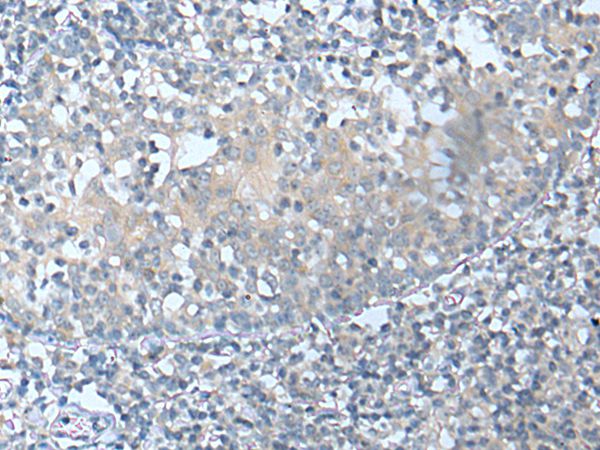

The image on the left is immunohistochemistry of paraffin-embedded Human tonsil tissue using CSF1 Antibody at dilution 1/25, on the right is treated with synthetic peptide. (Original magnification: x200)